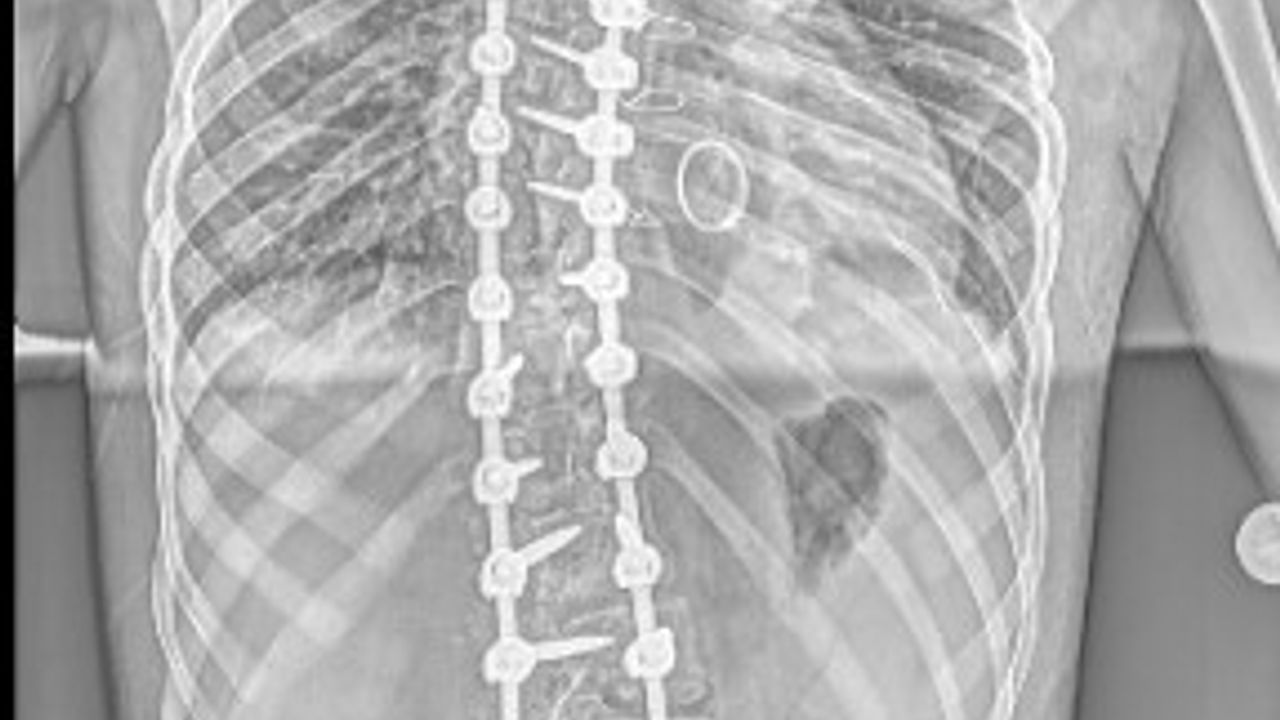

Lise öğrencisi Eren Sayın'ın, 4 yaşında kalp yetmezliği olduğu ortaya çıktı ve kalbindeki delik nedeniyle ilk ameliyatını oldu. 4 yaşında bu yana ilaç kullanan Eren, 1 yıl önce bu kez mitral kapak değişimi operasyonu geçirdi. Kalp rahatsızlığı ile birlikte skolyozu da bulunan Eren, ağrıları artından Ankara Etlik Şehir Hastanesi'ne başvurdu. Eren'in sırt bölgesinde 90, bel bölgesinde 70 dereceye ulaşan eğrilik tespit edildi. Eren, kalp kapağı ameliyatı nedeniyle kullandığı kan sulandırıcı ilaçlar kesilmeden biri 8 saat, diğeri 6 saat olmak üzere 2 seanslık riskli operasyonla skolyozdan kurtuldu. Eren, yüksek miktarda kan kaybı yaşamasına rağmen başarılı geçen operasyonun ardından sağlığına kavuştu.

Ameliyatı gerçekleştiren Etlik Şehir Hastanesi Ortopedi ve Travmatoloji Uzmanı Doç. Dr. Vedat Biçici, Eren'in kalp rahatsızlığı nedeniyle skolyozunun son dönemde hızlı ilerlediğinin tespit edildiğini söyleyerek, "Kalpteki problemlerinden dolayı riskli bir hastaydı. İlk ameliyatında ciddi kanaması olmasından dolayı ilk ameliyatını birinci seans olarak tamamlayamadan bitirmek zorunda kaldık. İmplantlarını yerleştirip, ameliyatı sonlandırdık. Genel durumu toparladıktan sonra birkaç hafta geçip, değerleri de normal değerlere geldikten sonra ikinci seans olarak tekrar ameliyata aldık. İkinci seansta omurgadaki düzeltme işlemlerini tamamlayıp operasyonumuzu bitirdik" diye konuştu.

Doç. Dr. Biçici, skolyoz cerrahisinin diğer cerrahilere göre daha riskli, daha zor olduğunu söyleyerek, "Çünkü omuriliğe çok yakın çalışmanız gerekiyor ve yerleştirdiğiniz implantlar yüzünden bazen milimetre düzeyinde yakın çalışıyorsunuz. Omurgayı düzeltirken omuriliğe hasar verme ya da omuriliğe bir problem oluşma ihtimali yüksek. Ondan dolayı riskli bir ameliyattır. Zaten cerrahi süresi uzun ve geniş bir alanda ameliyat yaptığınızdan dolayı bunlar hep riski artıran şeylerdir. Eren ayrıca kan sulandırıcı ilaç alıyor. Bunlar kesilemediğinden bu ilaçların etkisi altında ameliyata almak zorunda kaldık. Normalde bu ilaçlar ameliyat öncesinde kesilir, kanama riski azaltılır. Ama Eren’de bunu yapamadık. Bu da Eren’in ilk ameliyatta kan kaybını artırdı. İlk ameliyatta ciddi kan kaybı yaşadık, operasyonu yarıda bırakmak zorunda kaldık. Kan tablosu normal değerlere geldikten sonra ikinci seans ameliyata aldık. Onun için daha güvenli olacak şekilde iki aşamada ameliyatını tamamladık. Şu an durumu iyi. Fizik tedaviye başlayacak ve kademeli olarak normal hayatına dönecek" dedi. (DHA)